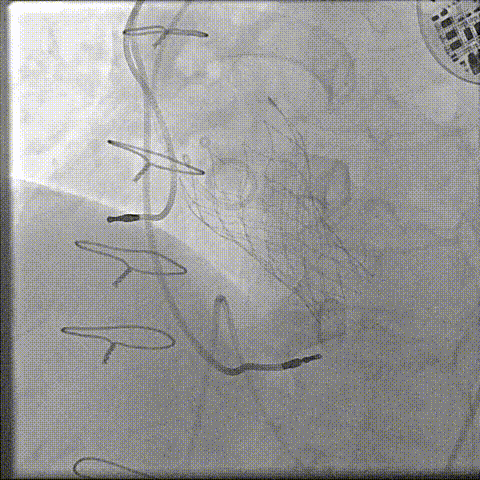

主动脉根部造影